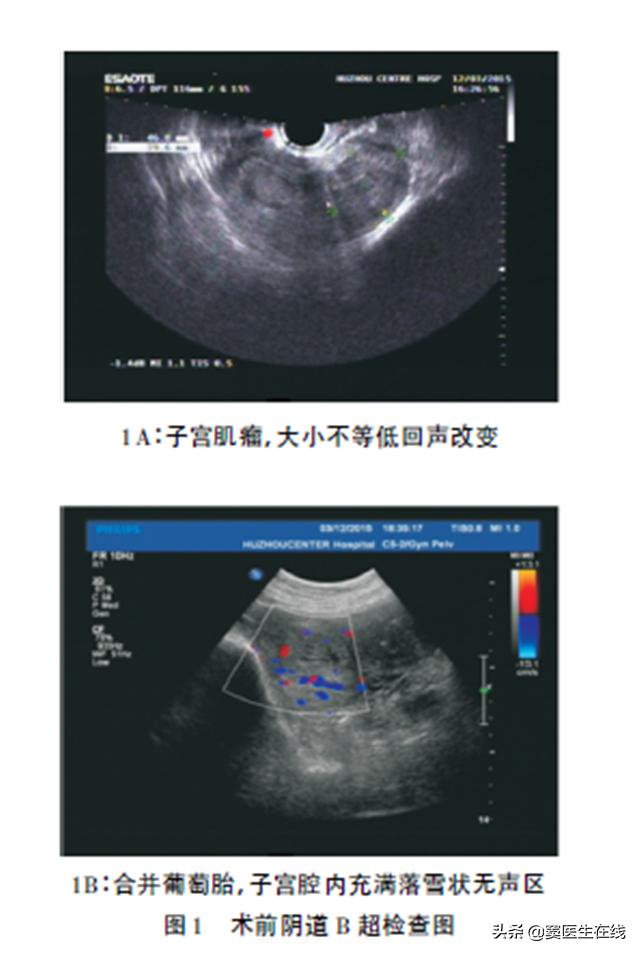

【辅助检查】:阴道超声检查示,子宫肌瘤( 较大者位于宫体部, 5.7cm×4.5cm×6.6cm,子宫内膜增厚欠均匀,范围7.1cm×3.0cm×4.3cm,内呈蜂窝样改变,葡萄胎待排( 见图1)

【诊断结果】:多发性子宫肌瘤、葡萄胎